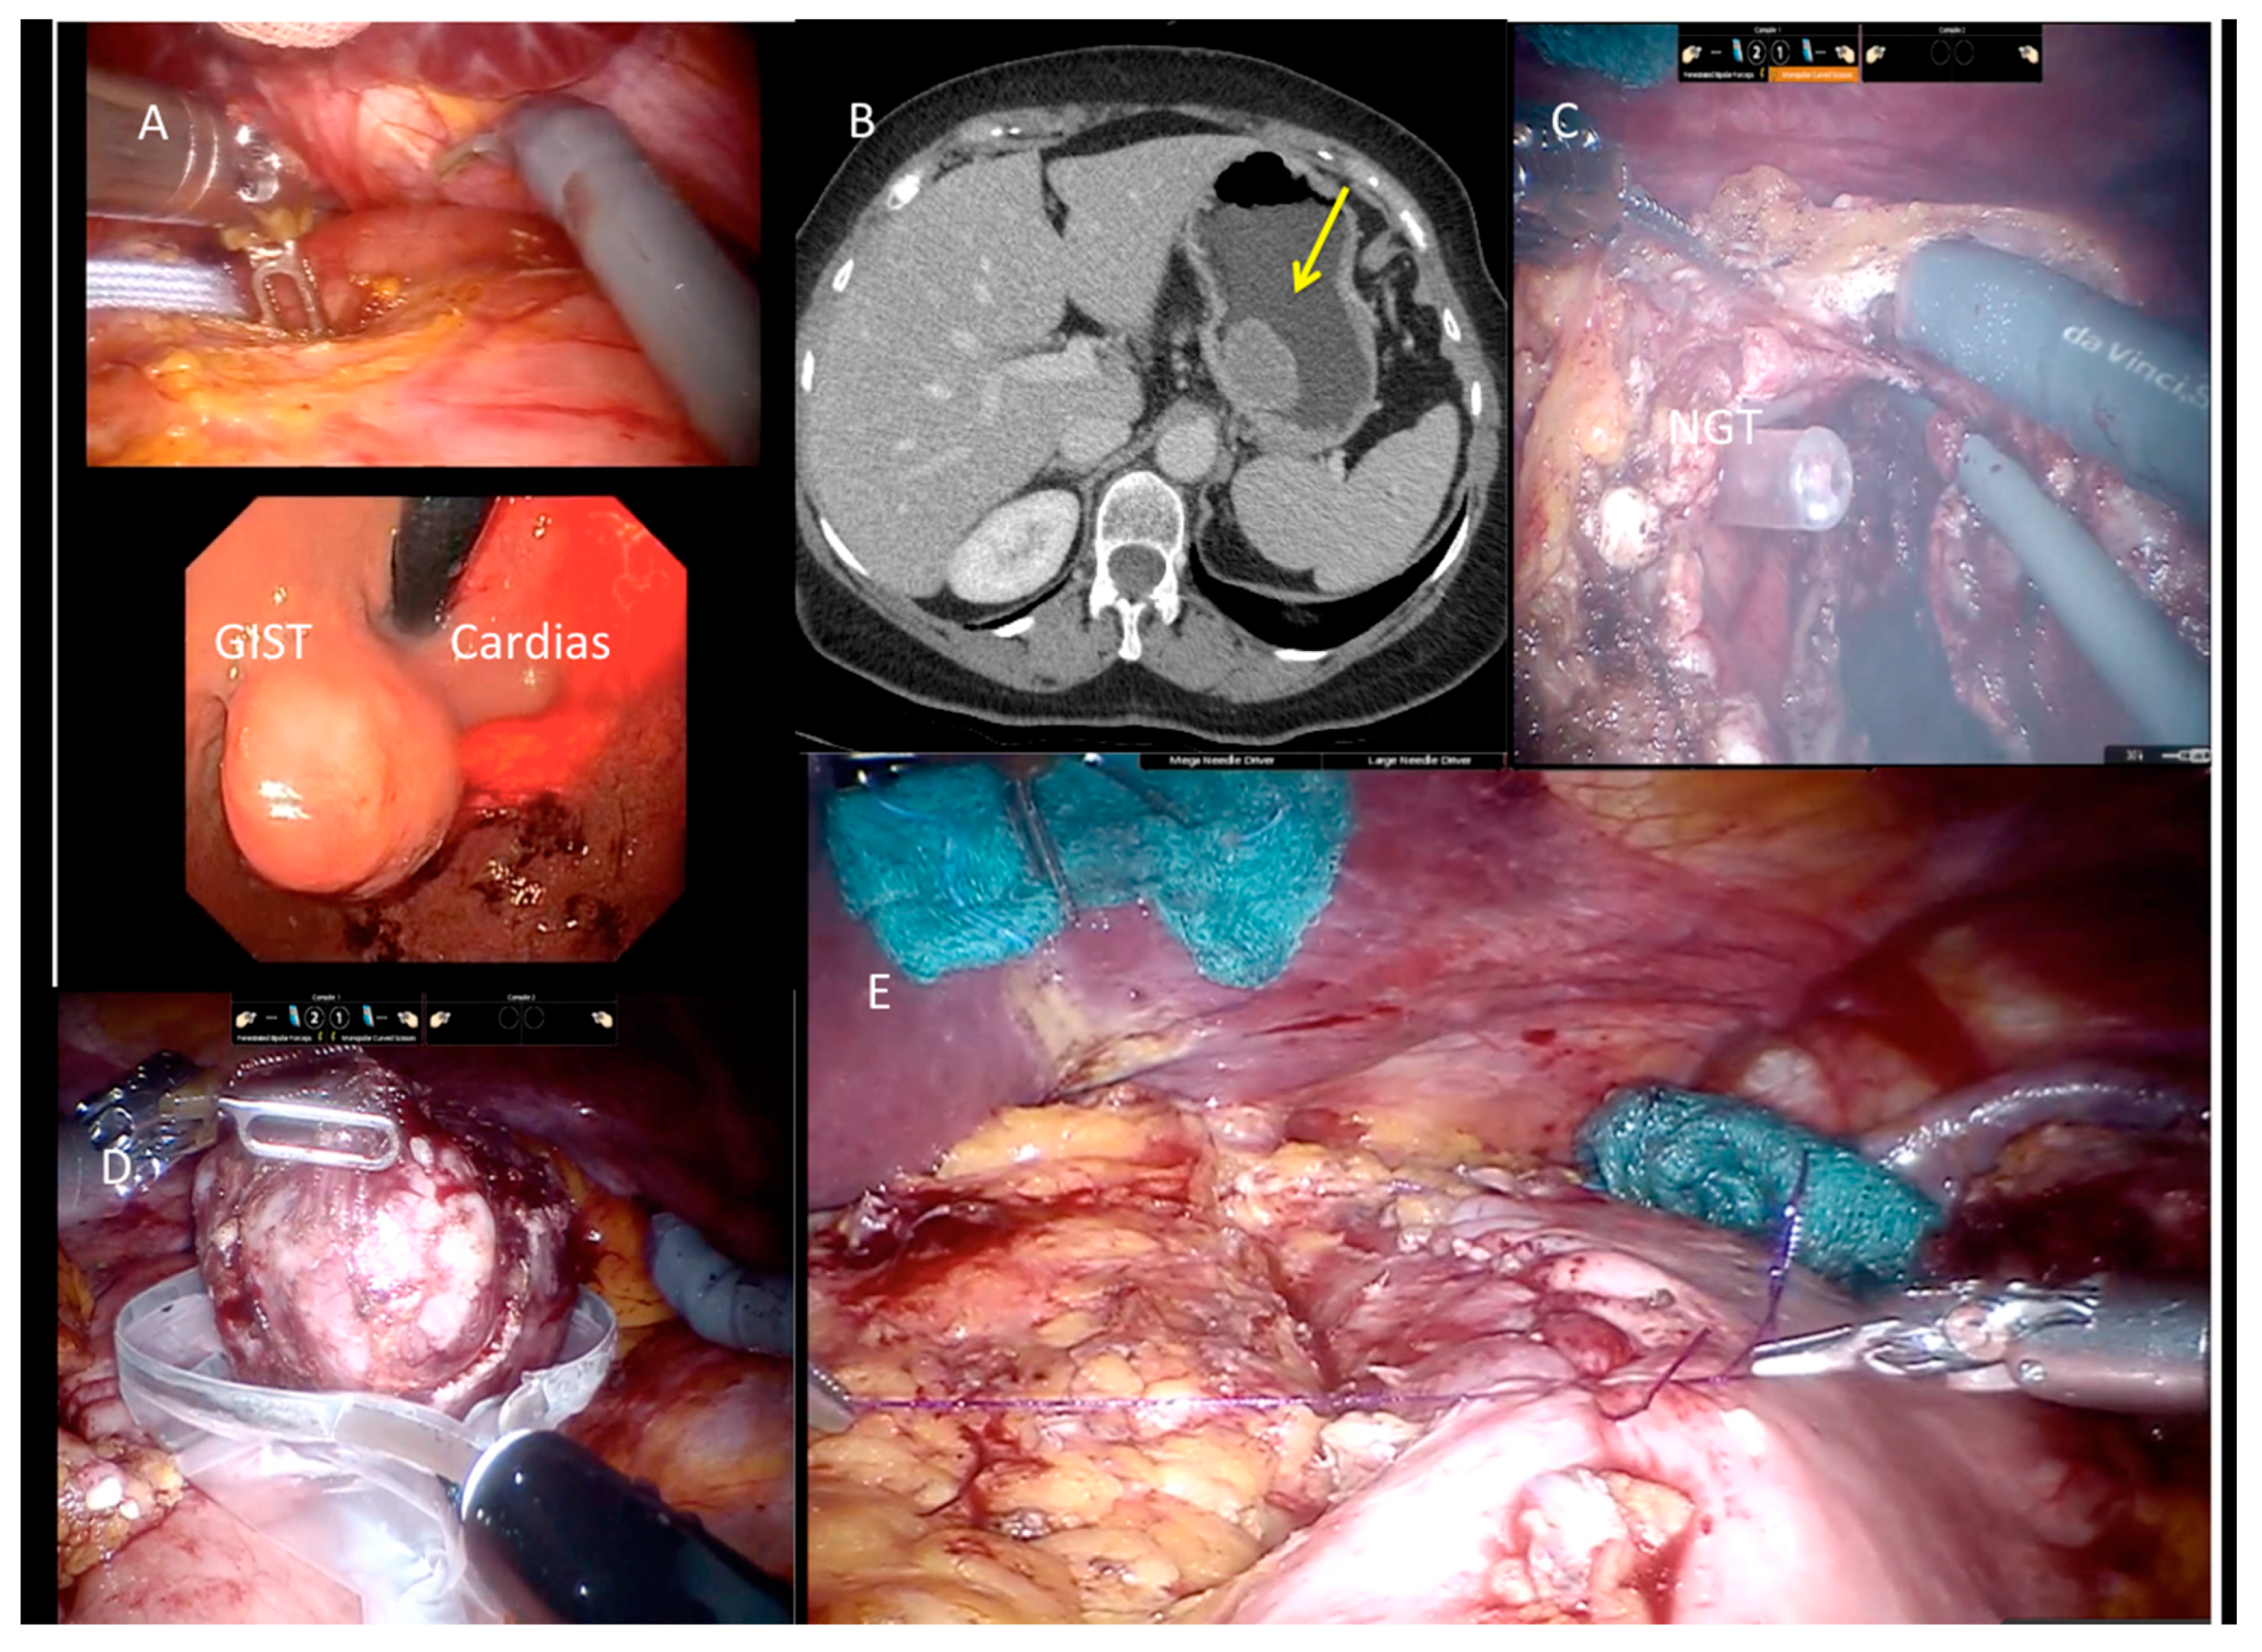

2.6. Technical Notes

2.6.1. Laparoscopic Approach

2.6.2. Robotic-Assisted Surgery